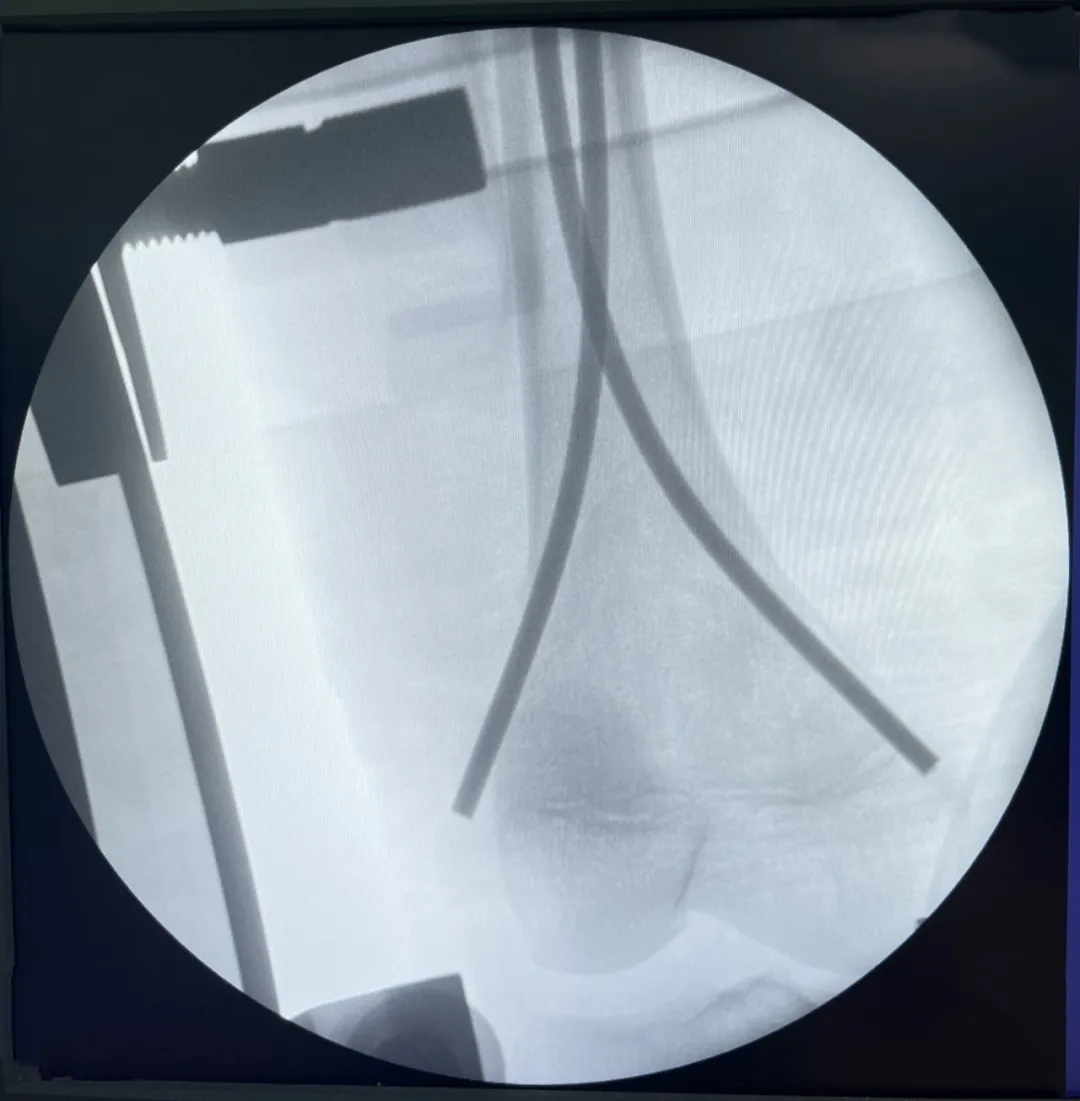

經(jīng)與家長(zhǎng)詳細(xì)溝通,我院骨科專家團(tuán)隊(duì)決定為患兒實(shí)施右股骨干骨折閉合復(fù)位彈性髓內(nèi)釘內(nèi)固定手術(shù)。術(shù)中,顧署光主任及趙飛副主任醫(yī)師在團(tuán)隊(duì)專家及手術(shù)室、麻醉科醫(yī)護(hù)人員的配合下,憑借精湛的醫(yī)術(shù)與熟練的操作手法,在樂樂患肢內(nèi)外兩側(cè)開了2個(gè)不足2cm小切口,對(duì)稱插入兩根彈性髓內(nèi)針,利用鈦合金或不銹鋼良好的彈性恢復(fù)力作用于骨骼,通過髓腔的3個(gè)接觸點(diǎn)轉(zhuǎn)換成推力和壓力,從而使骨折復(fù)位。手術(shù)成功,目前樂樂恢復(fù)良好。

內(nèi)外側(cè)兩個(gè)小切口